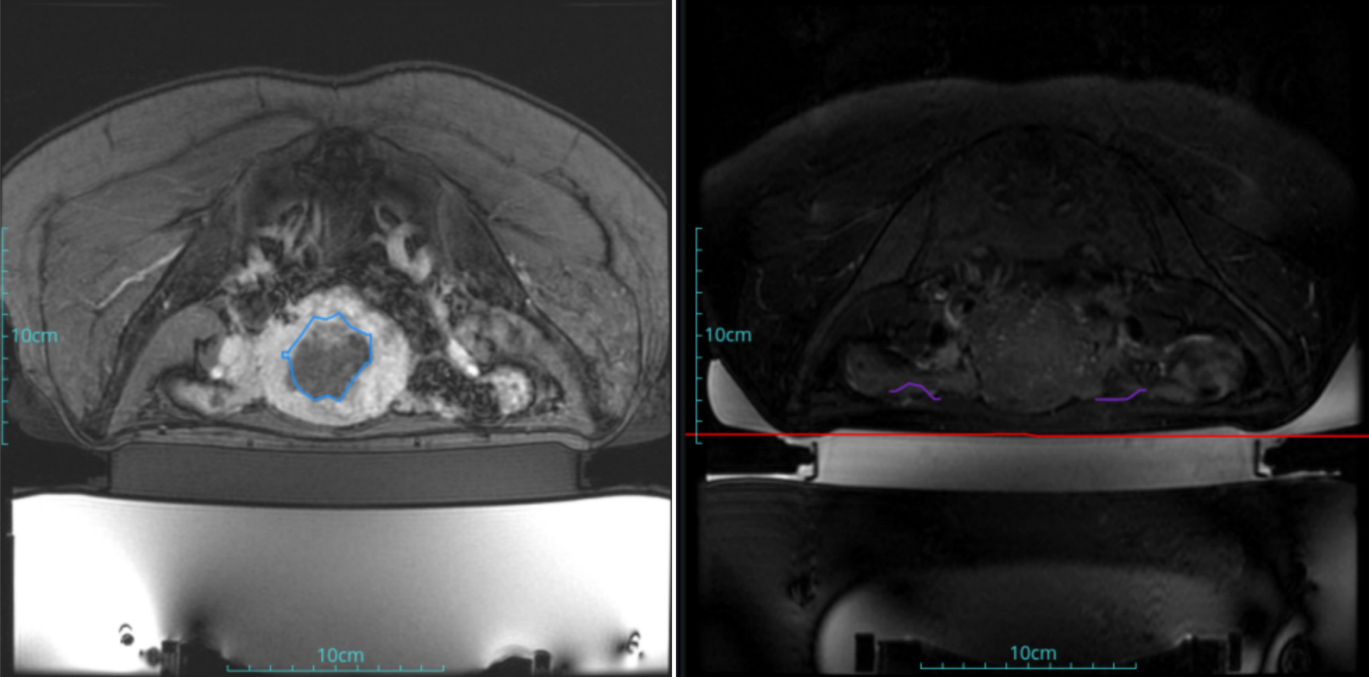

Diagnosis: Uterine fibroids

Tumor size: about 45*52*38mm

ROT depth: The ROT center of the tumor is mm from the skin

Postoperative evaluation: Postoperative enhanced imaging showed a good overlap between the ablation area (right) and the tumor area (left), the non-perfusion area was continuous and consistent.

Conclusion:It has a excellent ablation effect on this tumor, and the temperature rise curve during treatment is in line with expectations. The 240CEM area of each treated target is large, full and continuous.The ablation effect was very good,the NPV volume ratio was about 70%.